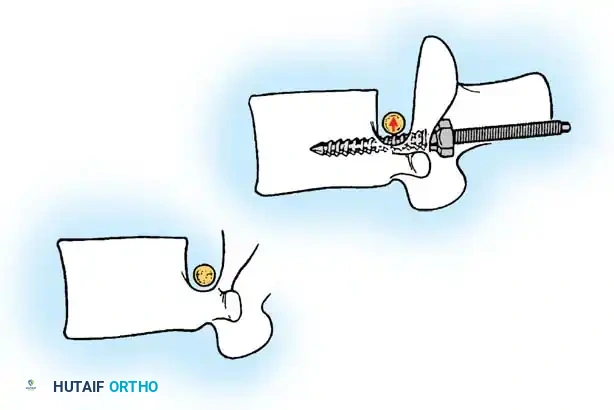

PRINCIPLES OF POSTERIOR SPINAL ARTHRODESIS

The ultimate goal of scoliosis surgery is not merely instrumentation, but a solid, lifelong arthrodesis. The classic extra-articular Hibbs technique has largely been abandoned in favor of comprehensive intra-articular fusion techniques that incorporate the facet joints.

The success of a spinal arthrodesis relies on a delicate interplay of factors:

1. Surgical Preparation: Meticulous removal of all avascular soft tissue and thorough decortication of the posterior elements.

2. Biomechanical Stability: Rigid segmental instrumentation to neutralize micromotion.

3. Biological Environment: Adequate delivery of osteoprogenitor cells and a vascularized graft bed.

4. Host Factors: Optimization of patient nutrition and strict cessation of smoking, as nicotine is a potent inhibitor of osteogenesis and significantly increases pseudarthrosis rates.

Biomechanics of Bone Grafting

Bone graft incorporates most effectively under compressive loads and is biologically disadvantaged in environments of distraction. Therefore, in scoliosis correction, if autogenous bone is limited, it should be preferentially concentrated on the concave side of the curve, which is subjected to compressive forces, rather than the convex side, which experiences tension. Furthermore, the farther the fusion mass is placed from the instantaneous axis of rotation, the more effectively it will neutralize movement across that axis.

FACET FUSION TECHNIQUES

With the advent of modern intra-articular fusion techniques and meticulous transverse process decortication, the pseudarthrosis rate in adolescent idiopathic scoliosis has plummeted to 2% or less.